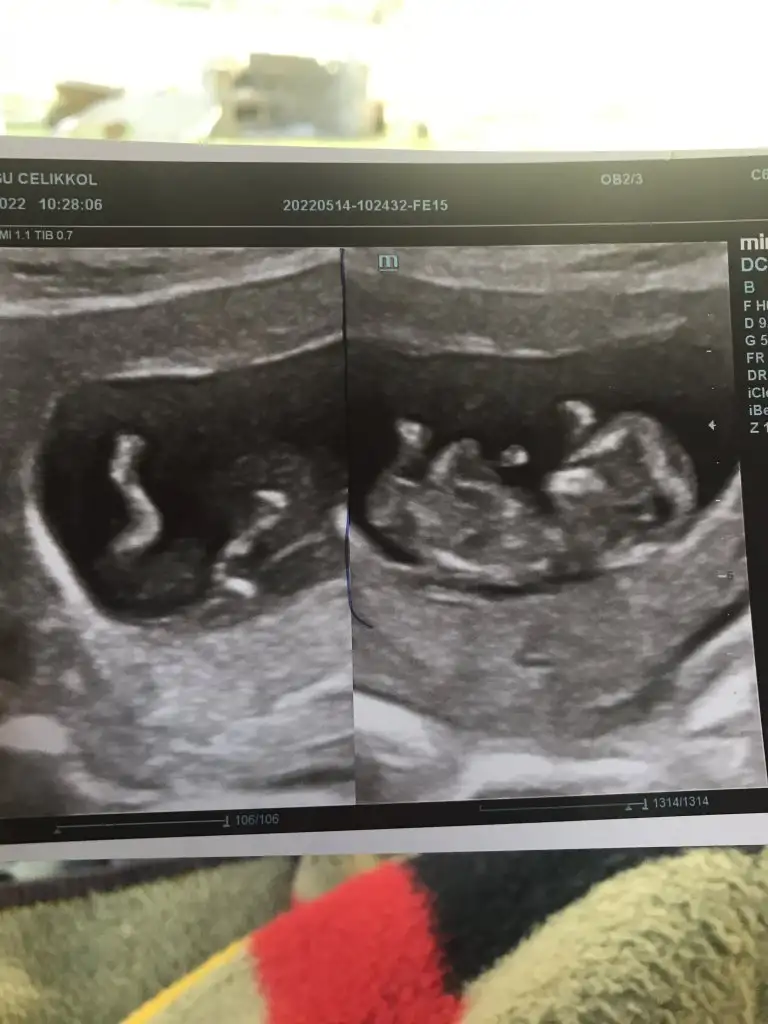

Banada tahminde bulunurmusunuz acaba,biri 6 haftalik digeri 9 haftalik,

DF51552A-B482-4254-81FB-8960F95AA8DE.webp

simdiden tesekkürler